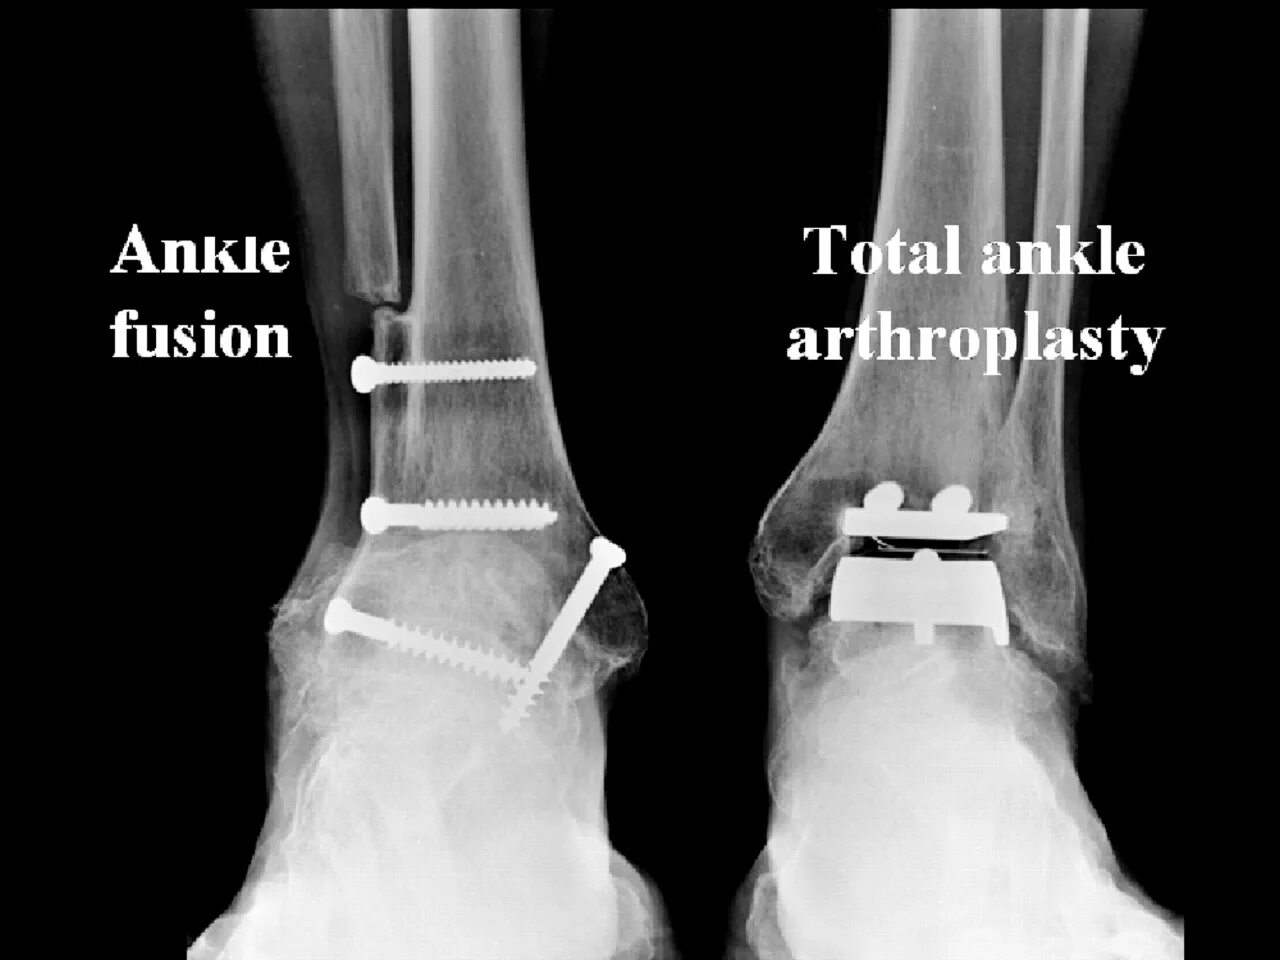

Артродез форум